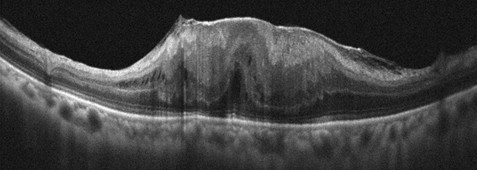

2022年馮先生左眼術後三年,偶然發現右眼看東西時也產生輕微的扭曲變形,就醫檢查右眼視力略為下降至0.8,也發現黃斑部皺褶(圖五)。因症狀輕微,雖在傳統的認定上是不需要立即接受手術的,林泰祺主任仍建議及早手術,有助於保留黃斑部功能並提升術後視力恢復的可能性。馮先生接受建議,術後右眼視力回復至1.0,看東西扭曲變形的情形完全獲得改善。

(圖五)共軛光掃描儀檢查顯示右眼黃斑部皺褶為前期的變化。